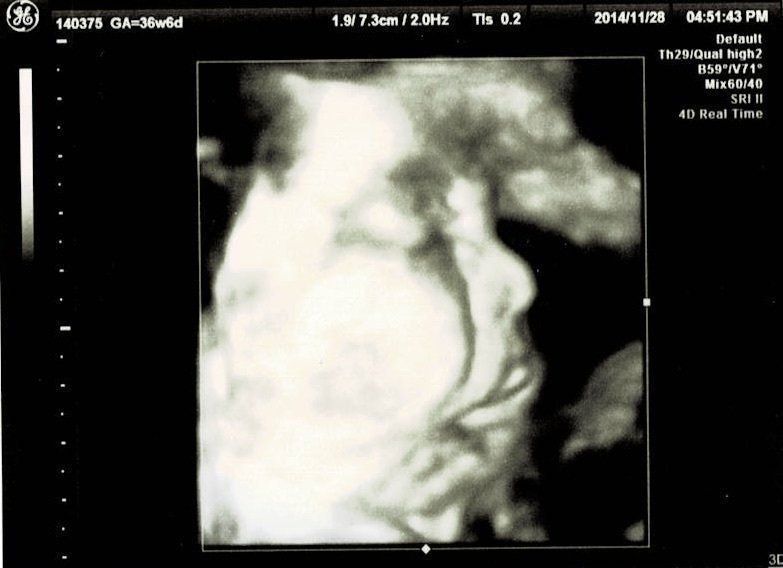

妊娠36週目エコー写真 NST実施 エコー中に赤ちゃんが大あくび!

ノンストレステストを受けました。検査中におなかの張りが計測されたようですが、私はその感覚が分かりませんでした。張りに気づかなかったことで、万が一、お産の兆候がわからなかったらどうしようと不安に。赤ちゃんは3Dエコーをしました。エコーをしているときに、なんと赤ちゃんが大あくび!あくびもするなんて本当に普通の赤ちゃんと変わらないのだなという気持ちに。ほっぺもふっくらとして、やっぱり輪郭はお父さんそっくり!